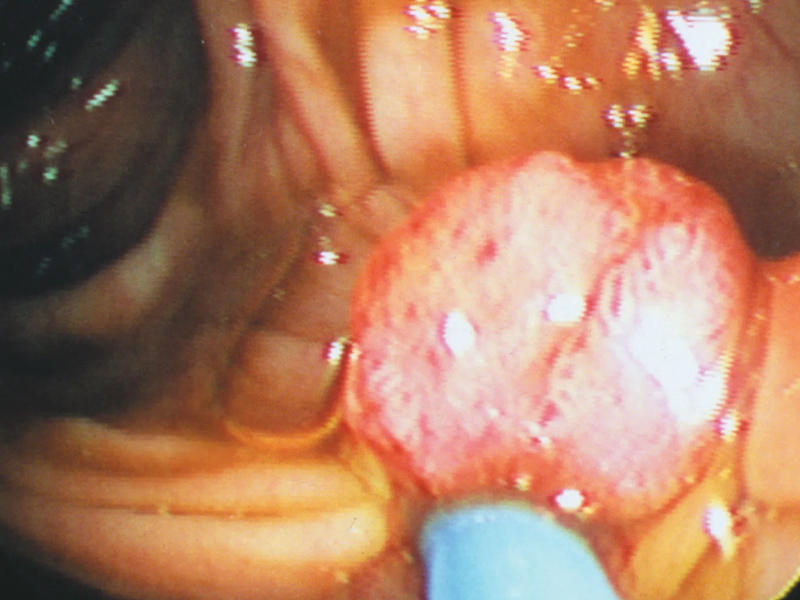

感染 Arcturus 的患者除了會出現喉嚨痛、流鼻涕、發燒、疲勞、咳嗽、頭痛、肌肉疼痛等症狀以外,最新病例顯示,部分患者已出現眼睛發癢以及結膜炎(紅眼病)。

報導稱,不少感染 Arcturus 的人都出現結膜炎或眼睛發紅痕癢的症狀,當中以年輕患者佔多。印度有兒科醫生提醒,這是一種不常在其他冠病病毒變種中註意到的症狀,或需進一步監測是否有關聯。

最近就有一名定居在澳洲的泰國男子發帖講述了自己在感染了新冠變種病毒 Arcturus 之後的一些症狀,其中出現的最為嚴重的症狀是眼睛嚴重發炎、幾乎快要看不見。